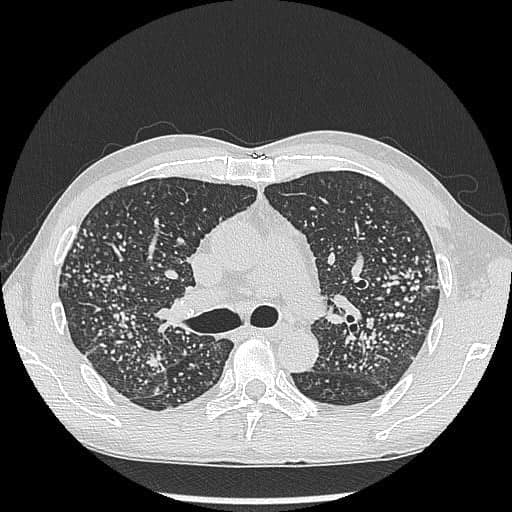

胸腔內科醫生蘇一峰在其facebook專頁發文指,該名40歲男子平日沒有吸煙習慣,但近幾個月出現不斷氣喘的情況,遂往醫院求醫。醫生一看,發現該男子的手指明顯是“杵狀指”,而且幾乎十只手指也變成“杵狀指”。醫生隨即安排他照X光,結果驗出肺結節,就如“滿天星”。

▲照X光發現,該男子長滿肺結節,如“滿天星”。(圖片來源:“胸腔內科醫生蘇一峰”facebook專頁)